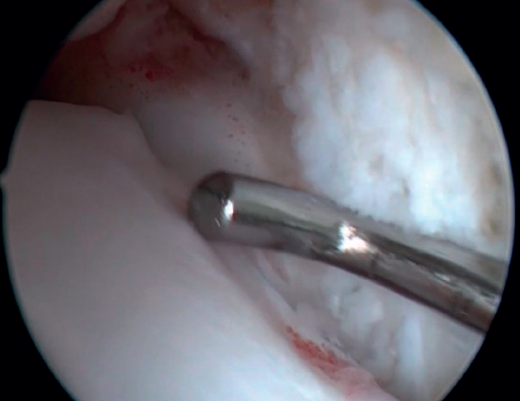

Resection of the osteophyte is performed by displacing from the top, and gradually reducing it until the joint zone is reached (Figure 2). A basket forceps can be used to resect the area closest to the joint (Figure 5). It is often useful to exchange the viewing and working portals in order to visualize and completely resect the osteophytes. In the case of soft tissue impingement, a 3.8 or 4 mm synoviotome is usually sufficient. The vaporizer is useful in the case of compact impingements, typical of post-traumatic conditions or re-interventions, and also for delimiting the bony part of the osteophyte before resection.

Bassett's ligament should be preserved as long as it does not have a pathological appearance, ruling out thickening, partial tears or reciprocal lesions on the anterolateral surface of the talus (Figure 6), which are associated with anterolateral or rotational instabilities. The peroneal insertion is used as a reference to locate the distal insertion of the ATFL. The deltoid ligament at the medial groove should be inspected if associated rotational instability is suspected. During arthroscopy, direct ligament repair can be performed using sutures and anchors.